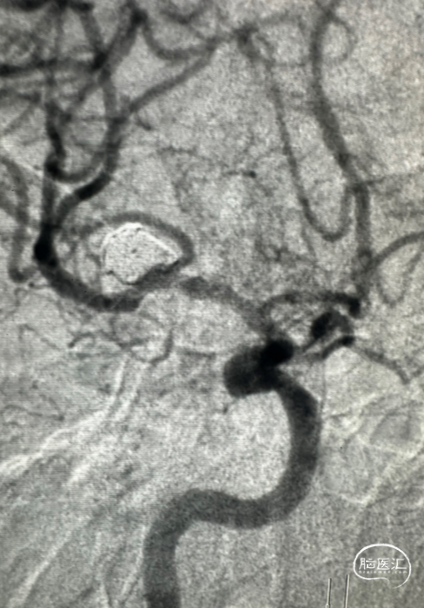

手术过程

微导管到位。

在瘤体置入首枚7*30cm弹簧圈成篮时,有少部分圈突至下干支狭窄处。

故半释放一枚LEO Baby 2.5*18mm支架,在瘤颈处进行推挤呈“灯笼”状;

再依次置入6*20cm、4*10cm、2*6cm三枚弹簧圈,全释放支架,完成治疗。

术后可见,通过支架的推挤“修饰”瘤颈,完美保留M2段下干支;各分支血管血流通畅。